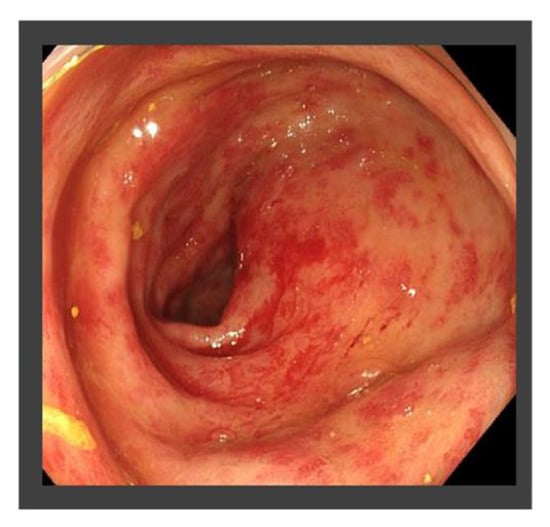

| X + 1 | July | Occasional bloody stool and the diagnosis of radiation proctitis (grade 1) by colonoscopy |